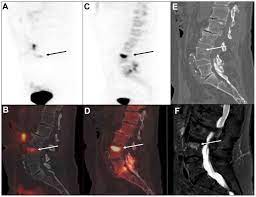

False Positive Diagnosis Of Disease Progression By Magnetic Resonance Imaging For Response Assessment In Prostate Cancer With Bone Metastases A Case Report And Review Of The Pitfalls Of Images In The Literature

False Positive Diagnosis Of Disease Progression By Magnetic Resonance Imaging For Response Assessment In Prostate Cancer With Bone Metastases A Case Report And Review Of The Pitfalls Of Images In The Literature from www.spandidos-publications.com